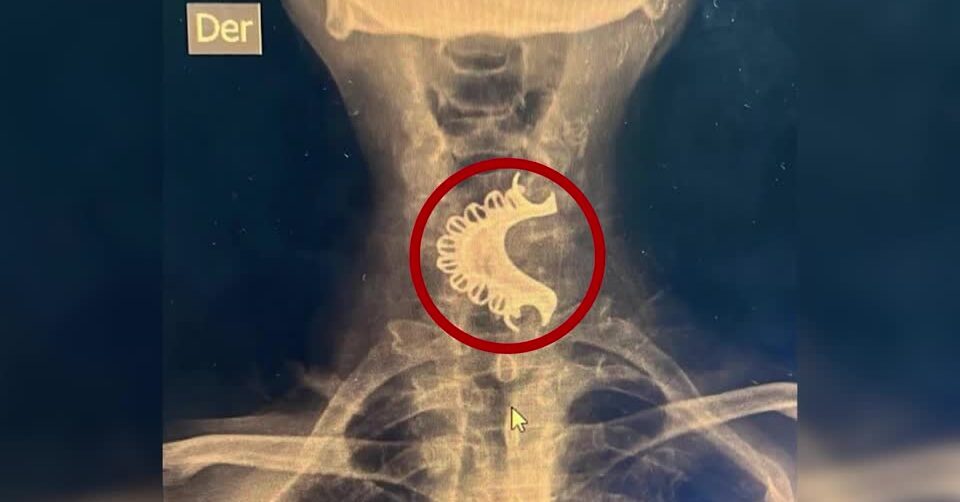

แพทย์ที่โรงพยาบาลชุมชนนำตัวคุณปู่เข้าเครื่องเอ็กซเรย์ พบฟันปลอมทั้งแผงติดค้างอยู่ในบริเวณคอหอยส่วนล่าง จึงสอดท่อขนาดเล็กลงไปในลำคอเพื่อช่วยเรื่องทางเดินหายใจ แล้วส่งตัวไปรักษาต่อในโรงพยาบาลที่ทันสมัยกว่า โดยแพทย์ได้วิธีส่องกล้องและใช้เครื่องมือดึงเอาฟันปลอมออกมาจากคอได้อย่างปลอดภัย คุณปู่ออกจากโรงพยาบาลแล้วหลังจากที่พักฟื้นอยู่ในโรงพยาบาลไม่กี่วัน.-816(814).-สำนักข่าวไทย

เครดิตภาพ : EsSalud